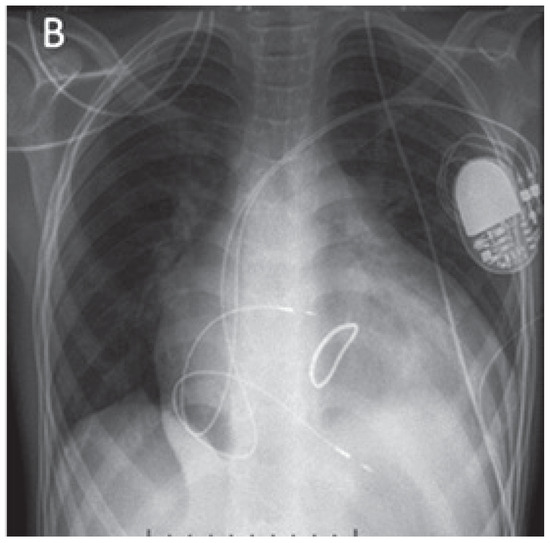

A 41-year-old women with Ebstein’s anomaly required tricuspid valve replacement six years ago. At that time a biological prosthesis was implanted. The tricuspid valve prosthesis became severely stenotic within five years. Instead of re-do surgery, th...